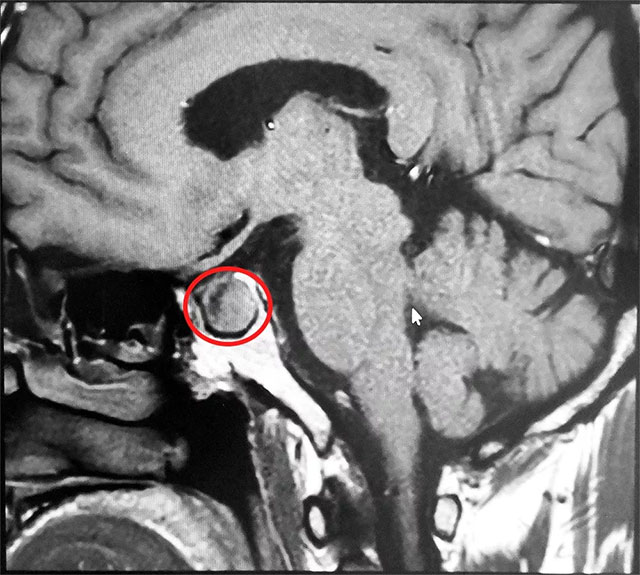

▲ 垂体大腺瘤超蝶鞍生长

患者MR鞍区MRI平扫+增强提示垂体占位,大小约1.7cm*1.4cm,专家考虑垂体腺瘤伴囊变。6B病区潘仁龙主任指出,该肿瘤属于罕见的垂体促甲状腺激素大腺瘤,对周围正常组织压迫导致患者头疼,已影响患者正常生活及自理能力,使患者精神压力日益增加,手术指征明确,应尽快行手术治疗。